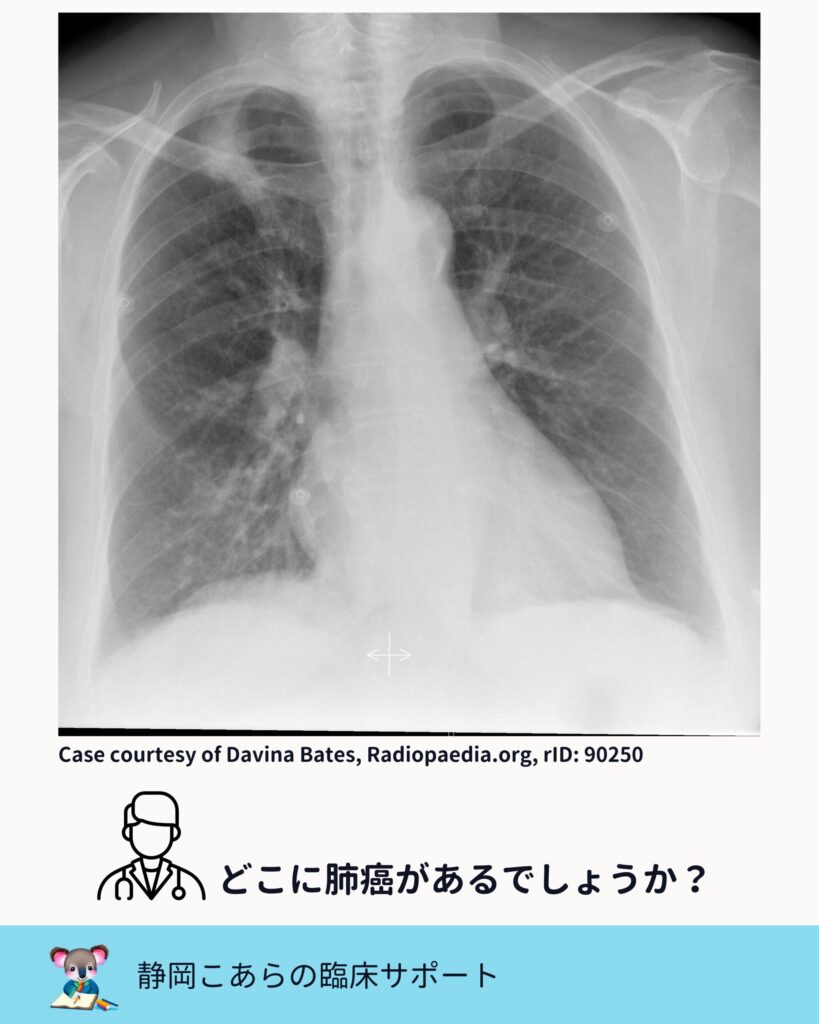

胸部レントゲンで肺癌が見えにくい部位は、

古くからいくつか指摘されています。

・心陰影と重なる部位

・肺尖部

・鎖骨と重なる部位

・肺門部

・肋骨や横隔膜と重なる部位

これは教科書的な知識であり、

Radiopaedia などの症例集を見ても繰り返し示されています。